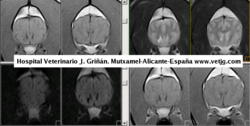

imágenes de resonancia del pastor alemán, donde es evidente la hemorragia cerebral |